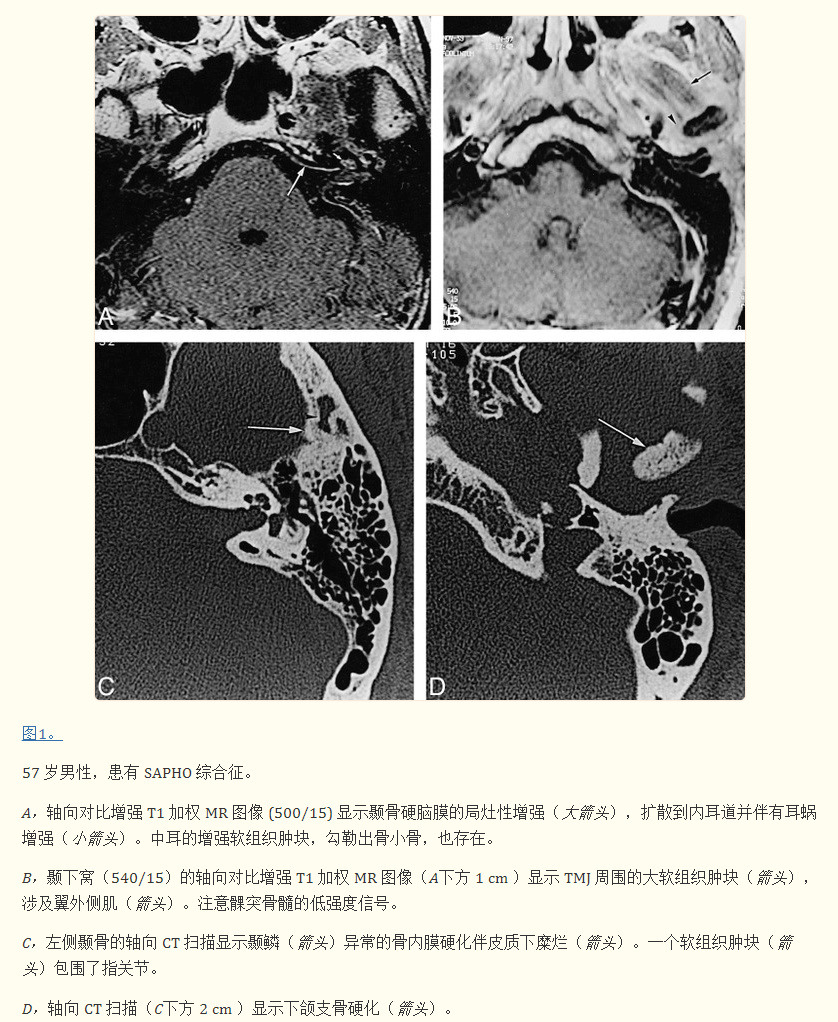

脑部增强磁共振成像显示覆盖左侧颞骨颅内部分的硬脑膜局灶性强化,延伸至内耳道至耳蜗轴和耳蜗。图1A)。显示了鼓室上鼓室部分的相关增强。T2加权图像显示迷路液高信号正常,前庭蜗神经正常。T1 加权图像显示累及左侧 TMJ 区域的大软组织肿块(图 1B)。颞下颌关节囊增厚并强烈增强。没有发现 TMJ 积液。下颌支和髁突的骨髓在 T1 和 T2 加权图像上均显示异常低信号强度,并且在给予对比剂后未增强。

高分辨率 CT(与 MR 研究在同一天进行)显示颞鳞和髁的皮质骨侵蚀,以及涉及下颌髁和支的弥漫性骨内膜硬化。图 1C 和 D)。颞鳞部分被骨重塑区域吸收。颞鳞的病变向后延伸至岩鼓缝,保留鼓骨和岩骨,向前位于蝶骨大翼,向下位于蝶骨内侧。相对于对侧正常的关节窝扩大,关节内或关节周围没有明显的钙化。正常充气的中耳部分被软组织肿块填充,包裹住踝关节的外侧部分。外耳道中既没有软组织肿块也没有骨质侵蚀。